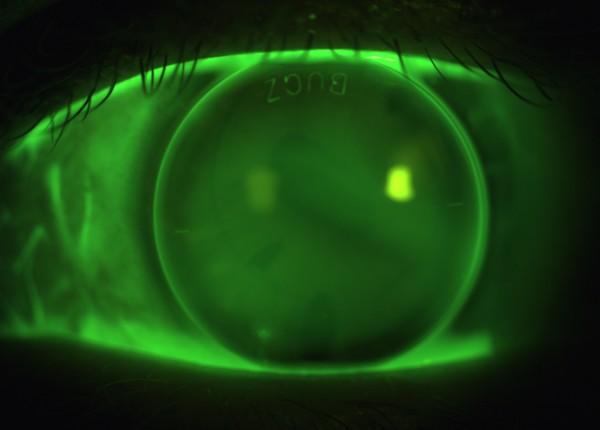

EyeSpace Bespoke Bitoric lens fitted on the left eye. Posted by CharlLaas November 22, 2016 No Comments Sodium Fluorescein image of EyeSpace Bespoke Bitoric gas permeable lens fitted on the left eye.